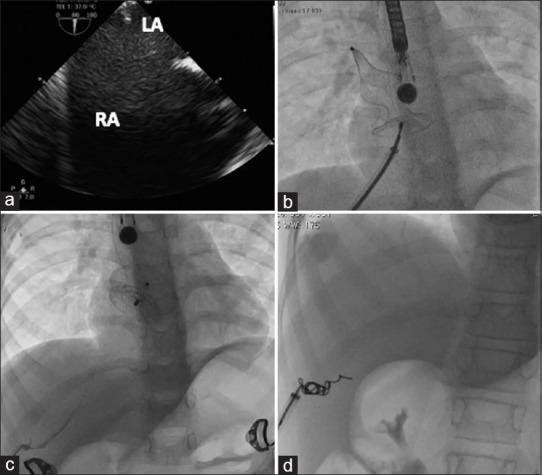

Transhepatic device closure of atrial septal defect in children associated with interrupted inferior vena cava.

Ann Pediatr Cardiol. 2022 Mar-Apr;15(2):160-163. doi: 10.4103/apc.apc_228_21. Epub 2022 Aug 19.

Abstract

Percutaneous transcatheter closure of fossa ovalis atrial septal defect (FOASD) is an established procedure. When femoral venous approach is unfeasible due to interrupted inferior vena cava (IVC) or occluded femoral veins, other interventional methods through transjugular, transhepatic approach, or surgical closure can be performed. We report two cases of transhepatic device closure of FOASD associated with IVC interruption successfully performed without any complications.